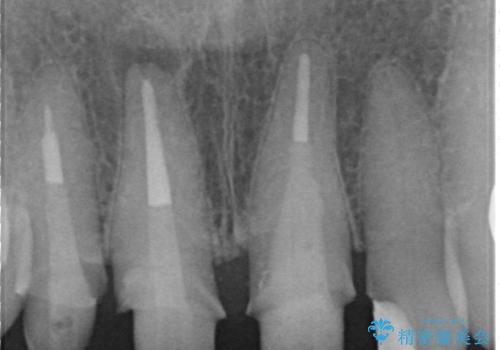

結婚式に合わせて根管治療からのやりかえを短期集中治療で計4回で終える計画を立てます。

- 40万円(仮歯・ファイバーコア・ジルコニアクラウン×3)費用は治療当時の料金となります

セラミック治療は外から見えるのはクラウンの色味・形態、歯肉の状態のみですが、X線撮影において現れるクラウンと歯牙の適合や、ファイバーコアの精度・根管充填の密度に、より長い予後を達成するための要素が含まれると考えます。